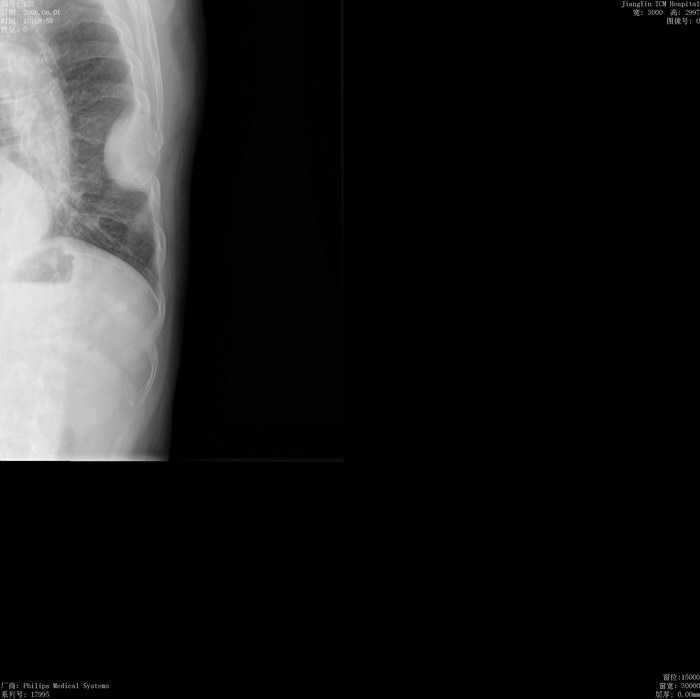

男性68岁.体检时发现左侧胸壁处肿块.肋骨破坏。询问病史无明显不适。请教大家。这是生长于肋骨的还是胸膜的或是肺内病变?

考虑肋股的病变[理由----如果来至于胸膜或肺的病变导致肋骨破坏应该考虑为恶性病变,那么临床症状应该明显如胸痛,胸水,恶病质等]----病变边缘清楚,外缘见薄壳影,其内似有小斑状钙样灶。考虑肋骨良性病变[内生软骨瘤,动脉瘤样骨囊肿等],恶性病变待排。建议ct检查

考虑肋股的病变,我认为先定位再定量,我认为应加照一个肋骨展开位(或许胸片正位就能看清)ct检查可免,病变边缘清楚,外缘见薄壳影,其内似有小斑状钙样灶。考虑肋骨良性病变[内生软骨瘤,动脉瘤样骨囊肿等],

定位于肋骨病变没有问题,病变呈膨胀性生长,骨壁菲薄,形成磨玻璃密度肿块,询问病史无明显不适。首先应该排除恶性病变。只能考虑良性病变,肋骨的良性病变如:骨纤维异常增殖症;骨嗜酸性肉牙肿等等,做ct会有利于观察病变细节。

根据影像学来解释应该是肋骨病变.如果是胸壁软组织肿块的话应该与侧胸壁呈锐角,如果是胸膜病变的话胸膜刺激征很明显.

支持12楼:定位于肋骨病变没有问题,病变呈膨胀性生长,骨壁菲薄,形成磨玻璃密度肿块,询问病史无明显不适。首先应该排除恶性病变。只能考虑良性病变。我认为肋骨的膨胀性病变如:骨纤维异常增殖症;转移瘤;结核;内生软骨瘤、巨细胞瘤、血管瘤、等。骨纤维异常增殖症一般范围大,且不应该出现软组织块影,故骨纤、内生软骨瘤、巨细胞瘤、血管瘤不考虑;结核一般发生于肋骨的两端,有软组织块影,一般有临床症状,暂时可不考虑;转移瘤在肋骨的转移要首先除外。

首先,它不会是肺内肿瘤,因为与胸壁交角成钝角.若是起源于肋骨,应该向 胸壁内外侧突出肿块.而这个病变主要位于胸壁内,同时有肋骨破坏,所以我考虑起源于胸膜.